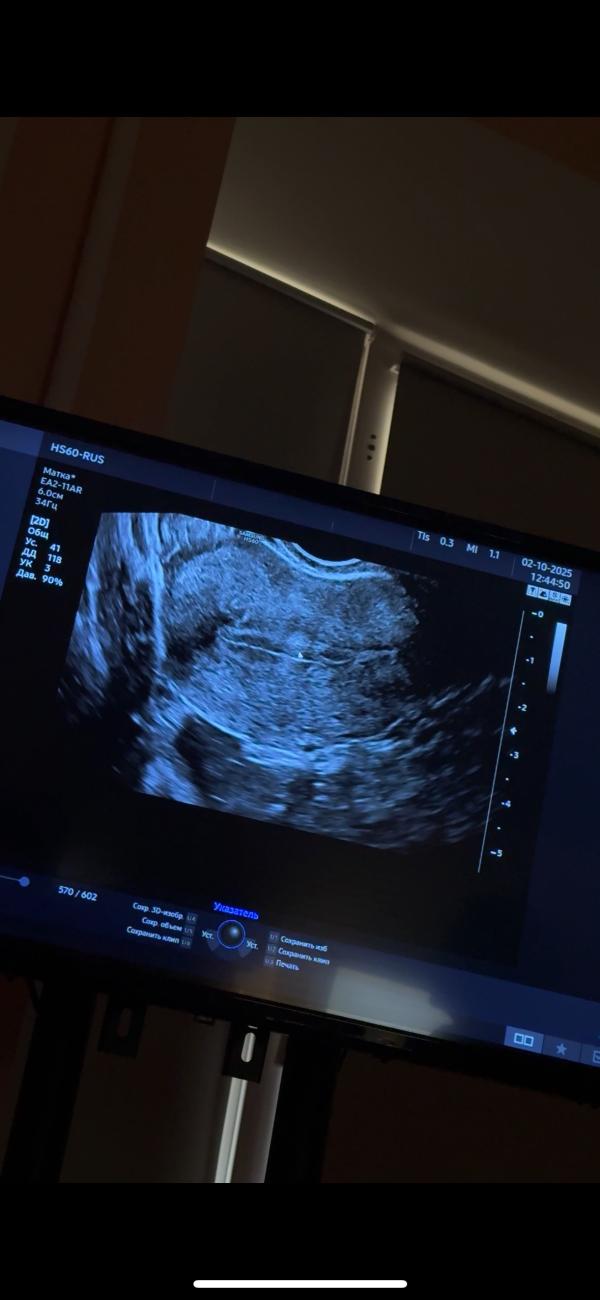

Что может быть на эндометрии после пункции фолликулов

Женсовет, что это может быть на эндометрии?

Кровотока нет, узист сомневается, что это полип

1 Цикл после пункции фолликулов

Просто на 5 и 6дц (2 разных узиста и разных аппарата было) не было ничего, а сегодня на 21, вот увидели что-то… просто везде пишут, что полип лучше всего видно в начале цикла… он мог появиться после?